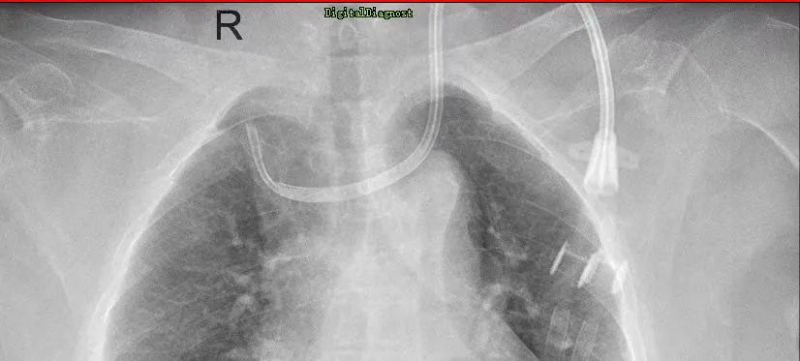

不久前,一位來自河源的患者到惠州市中心人民醫院博羅分院(博羅縣人民醫院)腎內科糾正導管位,這位日常是在當地的醫院進行腹透導管,但總有不適感產生,聽聞惠州市中心人民醫院博羅分院(博羅縣人民醫院)腎內科導管技術優秀,慕名場來求醫。這位病人在當地醫院進行血液透析,但導管流量不足,無法常見透析,到了惠州市中心人民醫院博羅分院(博羅縣人民醫院)就醫以后,腎內科主任吳勇對他進行了全面的檢查,發現該病人體內的導管已經像項鏈一般繞脖一圈,需要立馬糾正。吳勇馬上聯系了惠州市中心人民醫院的手足外科專家進行會診,經討論后對患者進行了球囊擴張術,并重新置入新的導管,術后患者透析順利,返回當地后也能繼續順利透析。該病人對惠州市中心人民醫院博羅分院(博羅縣人民醫院)微創置管導管技術表示了高度的認可,并定期回院復診。

2. 血管通路手術、DSA下的疑難置管,上腔靜脈造影+球囊擴張+置管術(靜脈置管、動靜脈內瘺、血液透析長期靜脈導管),彩超引導下經皮靜脈球囊擴張術,是血液透析病人血管通路狹窄治療的利器,可以減少病人痛苦,最大的可能保護病人的血管。